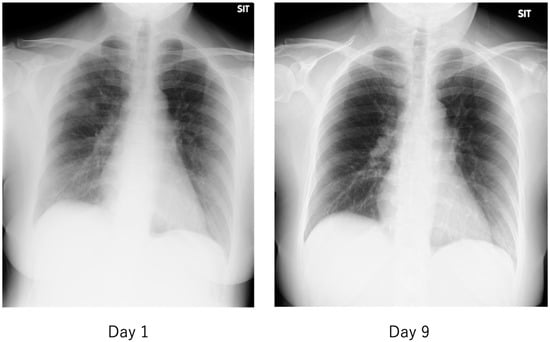

| Progressive multiple frosted shadows in both lungs | ||